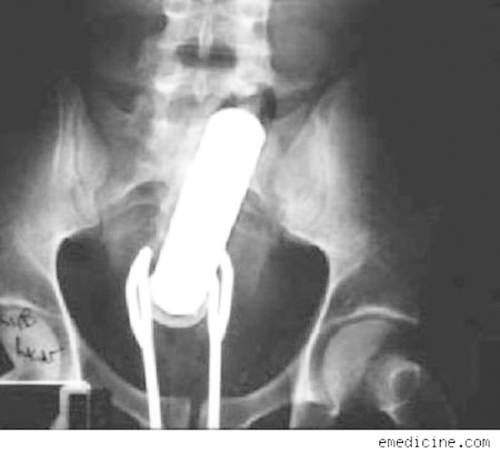

這個長條形的物體不是電動蘇格蘭,而是一罐噴霧式的香水~